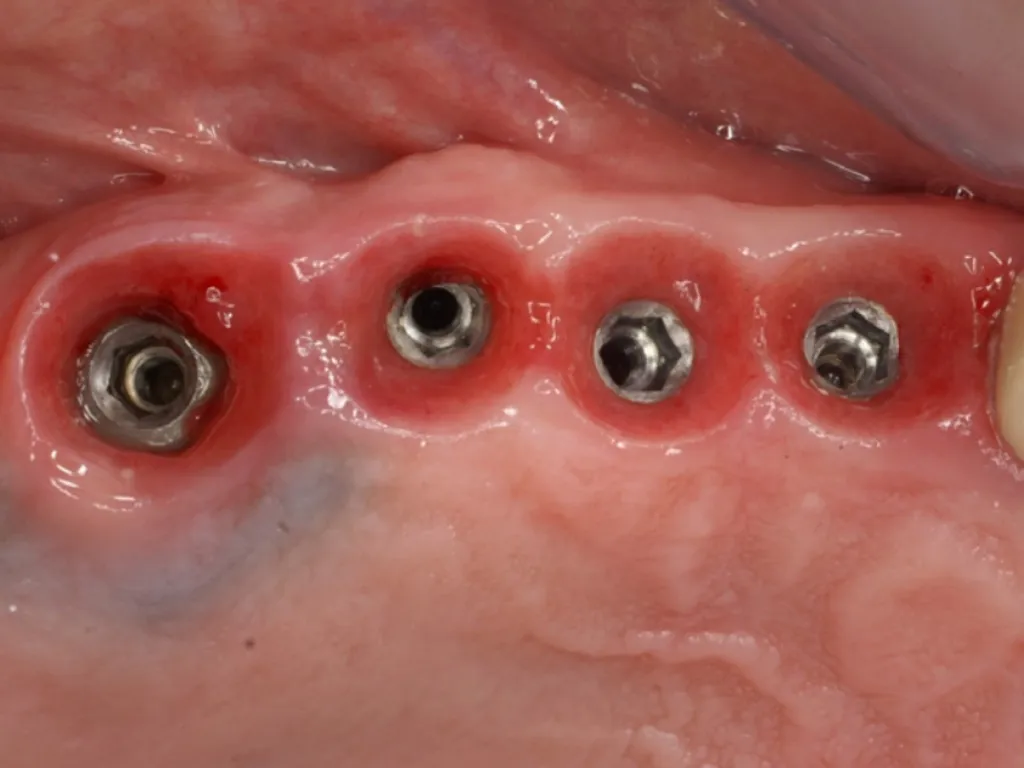

vaka_img

Baştan Sona Platform Switch

Dr. Kent Hamilton